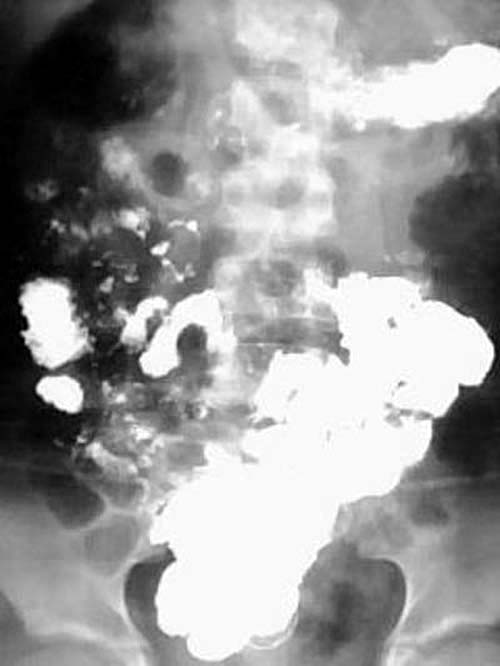

女性,12岁,因腹痛,恶心呕吐一周,腹呈绞痛,痛时可扪及包块,呕吐物为胆汁.大便不成形.于外院输液无好转(具体不详),遂转入我院,经对症治疗3天后好转,

服钡后两小时半摄片:

ped0661结果:中肠旋转不良伴中肠扭转.为手术所证实

本例是典型的中肠旋转不良伴中肠扭转的病例.为手术所证实.

本例临床表现是上消化道梗阻的表现.但初入院时外科诊断并不明确.透视未见明显异常(其他医生作的,具体不详),两次超声均未能明确诊断.入院后行禁食,胃肠减压,对症,输液等处理,约3天后腹痛缓解.拔胃管的当天吃了二个小包子,第二天作钡餐,钡餐示:十二指肠水平段不全梗阻(腹膜带压迫),空肠在左上腹小段盘曲后随即转向右,并于中腹部呈螺旋形下降(这是中肠旋转不良伴中肠扭转的典型表现),大部份回肠位于左下腹.因外科开的是上消化道钡餐,我已经把大部份小肠都看了,又到了下班时间,就没有继续往下追踪,如果断续追踪发现盲肠的位置异常,则可进一步的证实和肯定诊断.

中肠的旋转不良合并扭转在术前是可以确诊的,肠旋转不良作钡餐时不时可以见到,但合并扭转的并不多。根据本人体会及结合文献,中肠的旋转不良合并扭转,可以没有肠梗阻,但也可以有梗阻,甚至绞窄,坏死。几年前我也遇见过一位成人的小肠旋转不良伴扭转的病例.患者大约四、五十岁.没有明显肠梗阻,(遗憾的是胶片已销毁,不然可请老师们鉴别一下)。但不论有无梗阻,一旦发现有扭转均为手术指征。

钡餐检查可获得肠旋转不良的全部信息,包括十二指肠有无梗阻、十二指肠空肠曲位置、有无肠扭转及回盲部位置,是诊断本病的首选方法。钡灌肠造影发现回盲部在左腹部或右上腹部,可确诊肠旋转不良,但不能诊断是否并发中肠扭转。